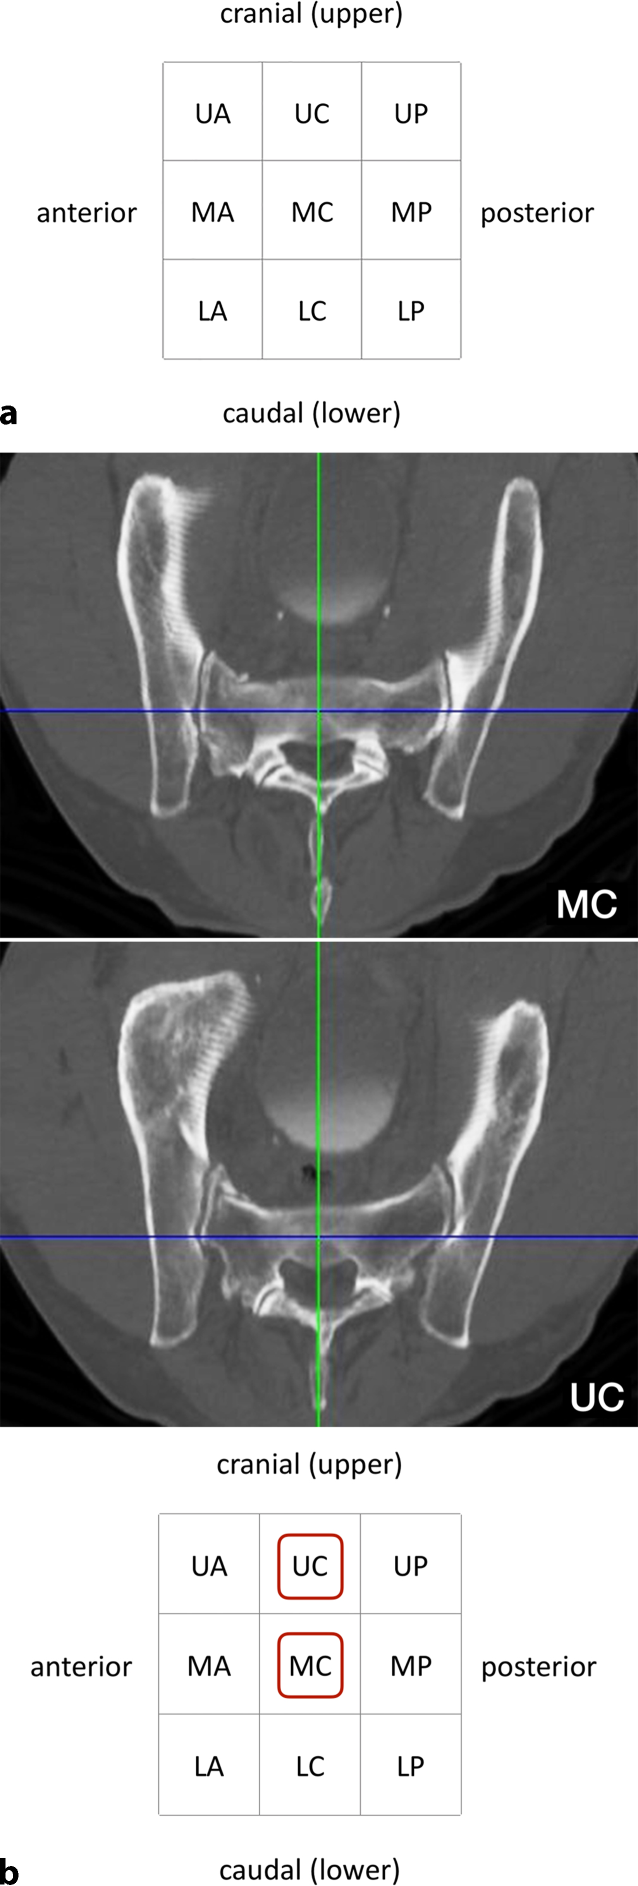

(Figs. 5, 67)

Fig. 5

Assessment of the starting point in the lateral view. Three views are mandatory for fluoroscopically controlled SI screw fixation: lateral view, inlet view and outlet view. The techniques for obtaining correct lateral, inlet and outlet views have been previously described in this journal [6]. In addition, the ideal angles for intraoperative fluoroscopic inlet and outlet views can be estimated from preoperative midsagittal computed tomography (CT) reconstructions [4]. It has to be kept in mind that ideal fluoroscopic inlet and outlet view angles are not orthogonal to each other and that the arc of angulation between both views rather averages about 67° [8]. a 55-year-old man with a minimally displaced transforaminal sacral fracture after a fall from height. The preoperative assessment shows no signs of sacral dysmorphism with a safe transverse MC corridor (i. e. both the starting point and the endpoint are located in the MC zone in the lateral view). There is also a safe inlet-oblique corridor (MC—MA), a safe outlet-oblique corridor (MC—UC) and an inlet-outlet-oblique corridor (MC—UA). It is planned to perform an SI screw fixation via a transverse MC corridor. b In the lateral view a central MC starting point is chosen for a planned strict transverse screw trajectory (MC). c The guide wire is advanced to the SI joint for a secure wire purchase in the bone. This additionally allows for assessing the wire trajectory in a lateral view. In the present case fluoroscopic control shows a slight cranial deviation from the planned strict transverse trajectory. Since the outlet-oblique corridor (MC—UC) was preoperatively assessed as safe as well, this trajectory is accepted for further advancement of the wire. U upper, M middle, L lower, A anterior, C central, P posterior

Bild vergrößern

Fig. 6

Fluoroscopic control in the inlet and outlet view. The wire trajectory is first controlled in an inlet view (a). It targets the central part of S1 (dotted line) and is therefore considered as safe. A more anteriorly directed trajectory would have been safe as well according to the preoperative planning (MC—MA). b The wire trajectory is then controlled in an outlet view. It follows the MC—UC trajectory, which is safe according to the preoperative planning (MC—UC). U upper, M middle, L lower, A anterior, C central